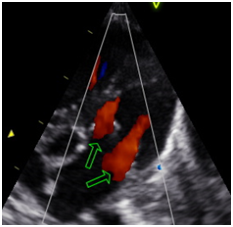

Figure 3 Long Axis 5 cameras.

Figure 4 Long Axis 5 cameras. Double mitral apparatus. Mitral presence of two flows.